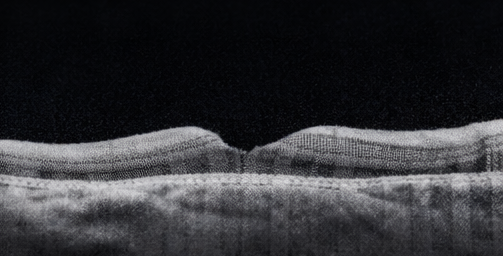

Spectral-domain OCT of the right eye confirmed macular detachment with accumulation of subretinal fluid beneath the fovea and loss of normal foveal contour.

The outer retinal layers showed early disruption of the ellipsoid zone, suggestive of photoreceptor stress without established atrophy. OCT imaging of the left eye was normal.

At one-week follow-up, fundus examination confirmed complete retinal reattachment with gradual absorption of intraocular gas. OCT imaging at four weeks demonstrated resolution of subretinal fluid and partial restoration of the foveal architecture.

At three-month follow-up, BCVA in the right eye improved to 6/18. The patient reported marked improvement in central vision, although mild metamorphopsia persisted. The retina remained anatomically attached, and OCT showed continued improvement in outer retinal integrity.

OCT has emerged as an indispensable tool in evaluating macular involvement, providing insights into photoreceptor integrity and enabling postoperative monitoring. Restoration of the ellipsoid zone on OCT correlates strongly with visual recovery [5].